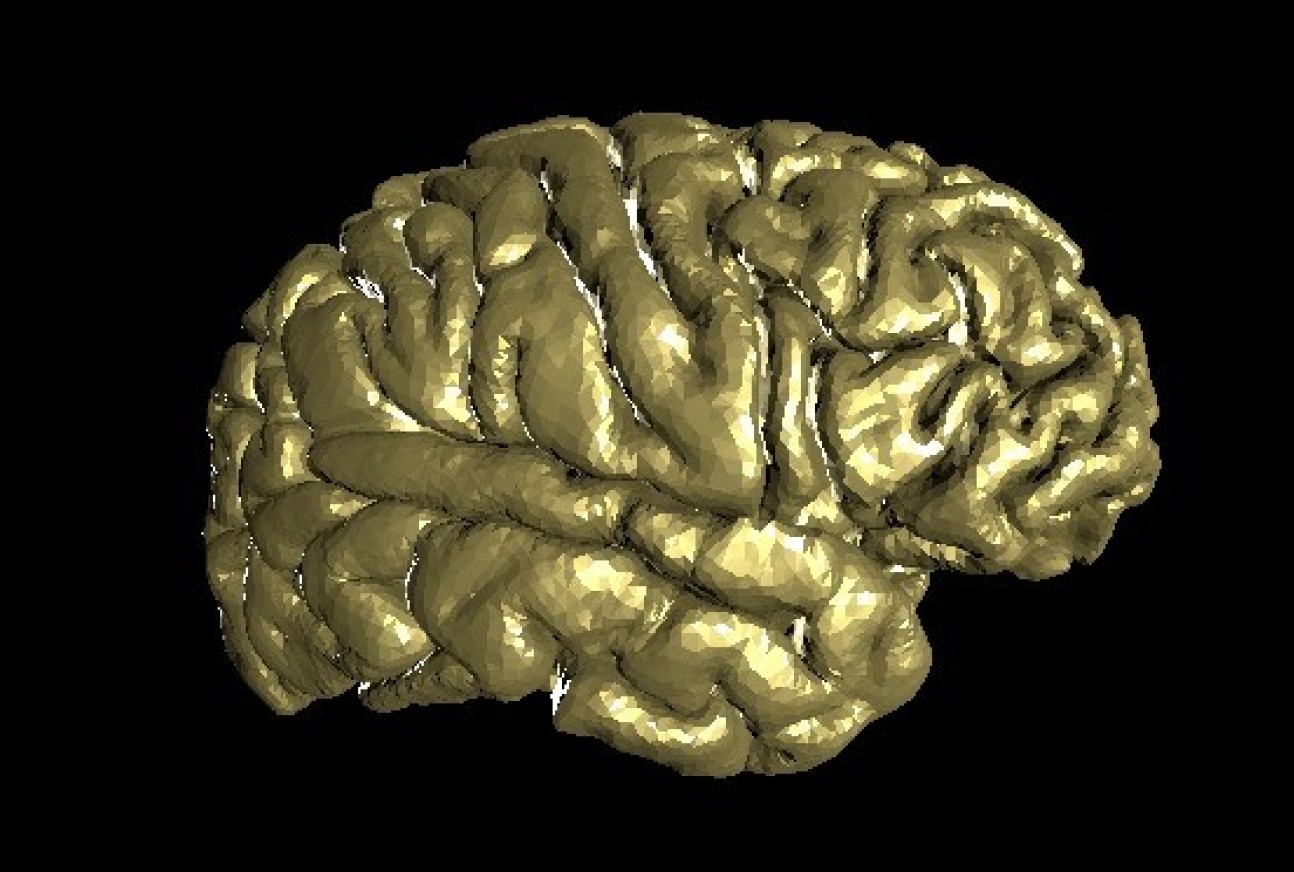

Golden Brain - Brian Schilder (PhD Student: Skene lab)

"3D surface reconstruction of the brain of the artist from 2D structural MRI scans, rendered with three.js."